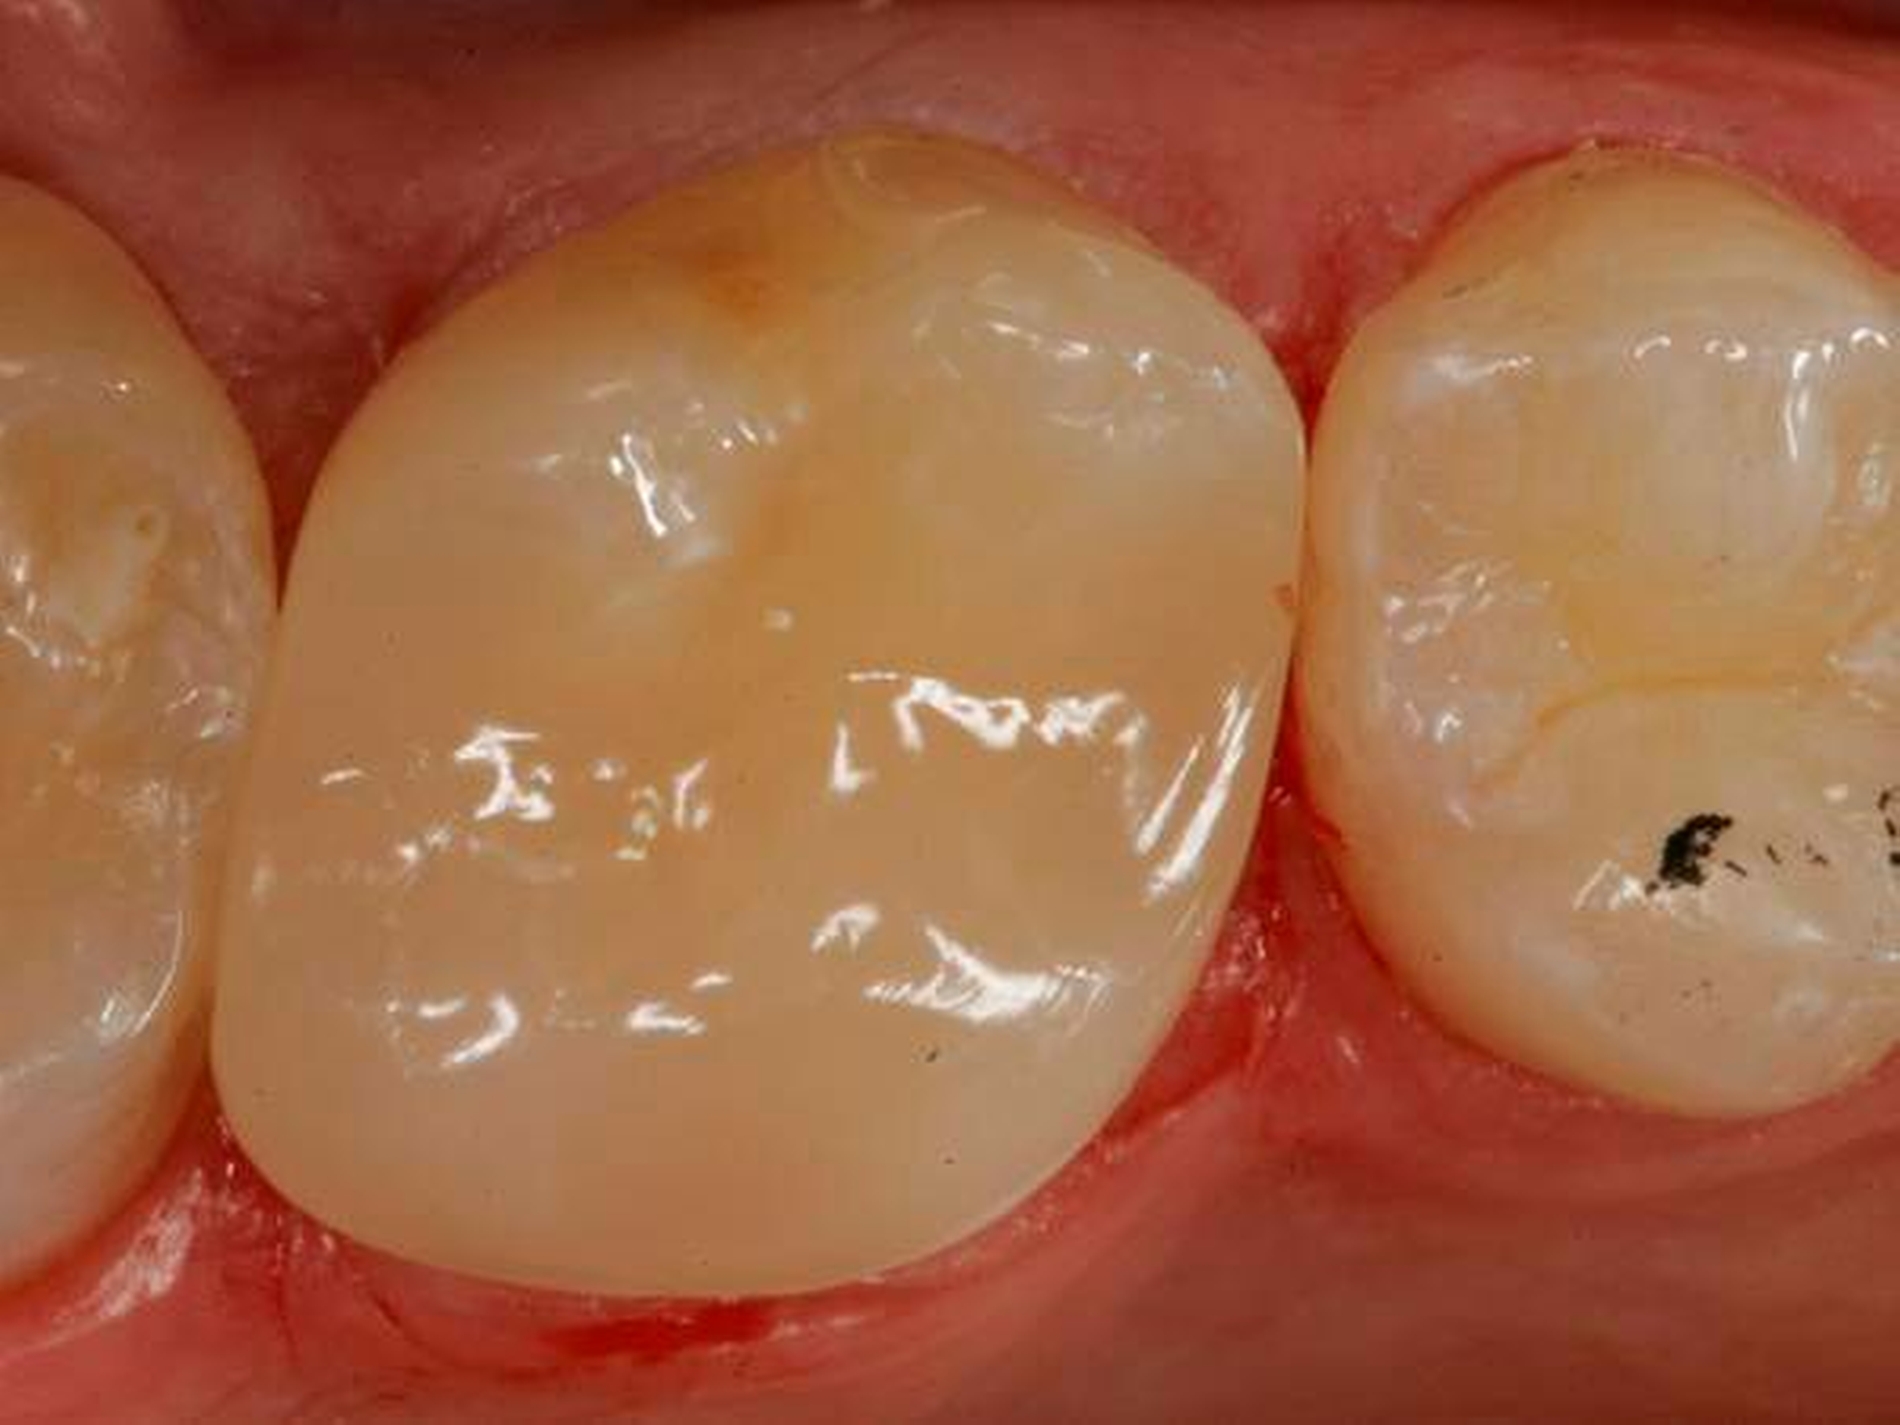

Abbildung 4 zeigt die fertig ausgearbeitete und polierte Restauration unmittelbar nach Behandlungsabschluss, Abbildung 5 bei einer weiteren Kontrolle nach einem Jahr: Der Zahn war inzwischen komplett beschwerdefrei, zeigte im Sensibilitätstest vergleichbare Reaktionen wie die Nachbarzähne. Die Oberfläche erschien allerdings etwas matt, was aber durch eine kurze Nachpolitur (Sof-Lex Polierrad „sehr fein“, 3M) wieder in eine hochglänzende Oberfläche verwandelt werden konnte (Abb. 6). Die Restauration integrierte sich ästhetisch und funktionell optimal in die umgebende Zahnhartsubstanz.